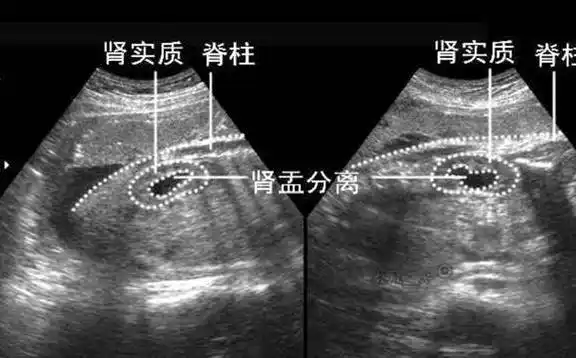

b超单上的"肾盂分离"是啥意思?和性别有关系吗?